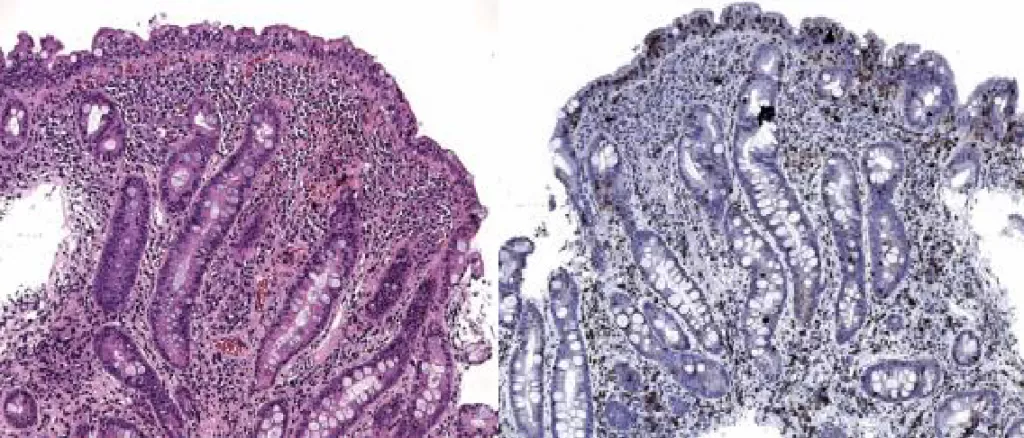

Стадия Marsh 3B (деструктивная, субтотальная атрофия ворсинок)

Характеристика: высота ворсинок резко снижена, крипты глубокие, снижение соотношения ворсинка/крипта (0,8:1 и менее), количество МЭЛ значительно увеличено |